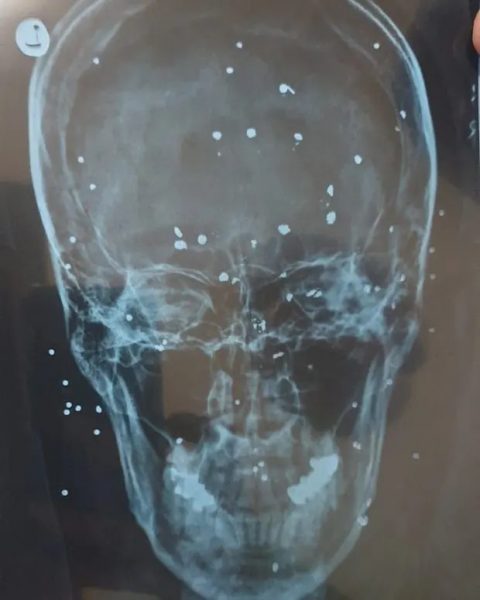

Οι αξονικές με τα τραύματα

Source: Guardian/ Εδώ φαίνεται ο πυροβολισμός στο πρόσωπο